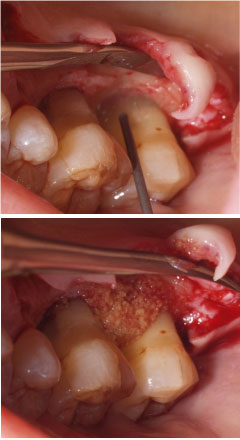

外科手術(中等度・重度歯周病の治療)

組織付着療法![]() |

![]() |

|

| 歯周病が進行したケースでは盲目下でポケット内の歯石を確実に除去するには限界があります。 | 局所麻酔をした後、歯茎を切開し、明視下にて歯根面の歯石や炎症組織を取り除き、歯周ポケットの除去をおこないました。 |